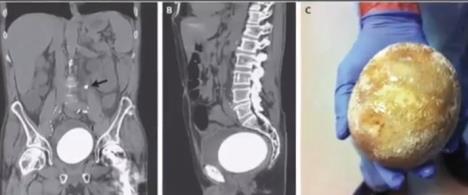

On je trpeo veliki bol na levoj strani i imao je probleme prilikom uriniranja, pa je otišao u Hitnu pomoć u bolnici Sent Meri na Long Biču. Na skeneru su mu primetili dva kamena. Mali je bio u delu koji povezuje njegove bubrege sa bešikom, a pravo "čudovište" od kamena je pronađeno u samoj bešici.

Kamen je imao težinu od 770 grama, tako da je malo lakše od nojevog jajeta koje može da teži i do 1,5 kilograma.

Međutim, teško da kamen može tako lako da poraste do ove veličine, pa se ovaj pacijent posmatra kao poseban slučaj. Njemu su pre deset godina zbog agresivnog oblika raka uklonili bešiku i ugradili novu, koju su napravili od komada njegovih creva. Ovo ga je učinilo podložnim za mnoge bolesti.